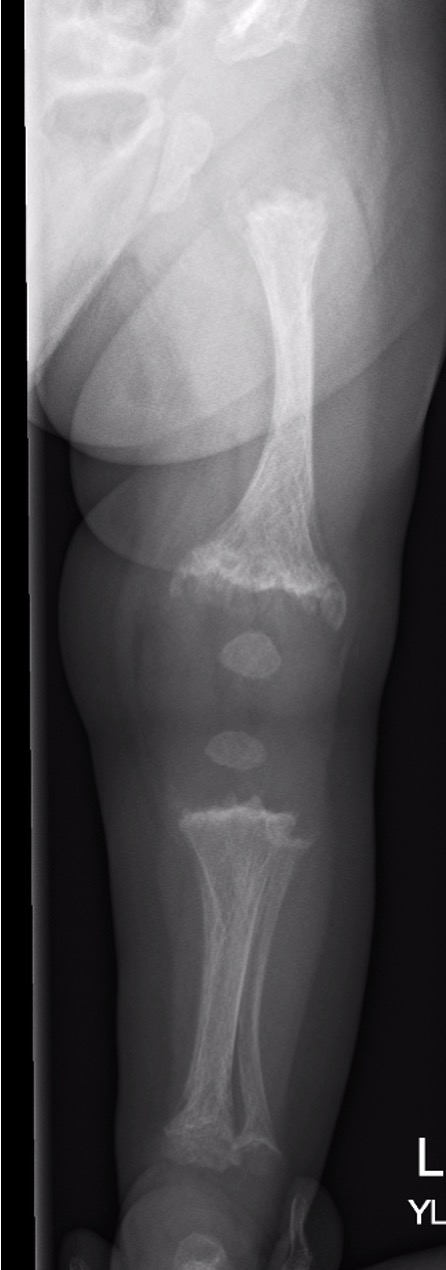

Metaphyseal changes of tubular bones

- normal epiphyses

- metaphysis adjacent to physis very broad and mildly scalloped

Erlenmeyer Flask Deformity

- striking bulbous metaphyseal expansion long bones

Hips

- coxa vara

Knees

- genu valgum